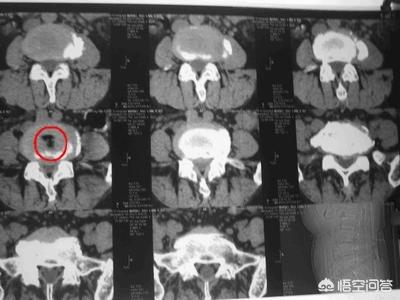

如果我猜的没错的话,你应该是做的腰椎间盘CT,在报告中这么写的,一般描述是椎间盘内可见气体密度影,在影像学上也叫椎间盘内真空征。

这是由于椎间盘内髓核脱水和变性,使髓核内积气的真空现象。椎间盘内气体的存在是一种变性征象,不表示出现这个就一定会发生腰椎间盘突出,当然也是可以同时发生腰椎间盘突出的!